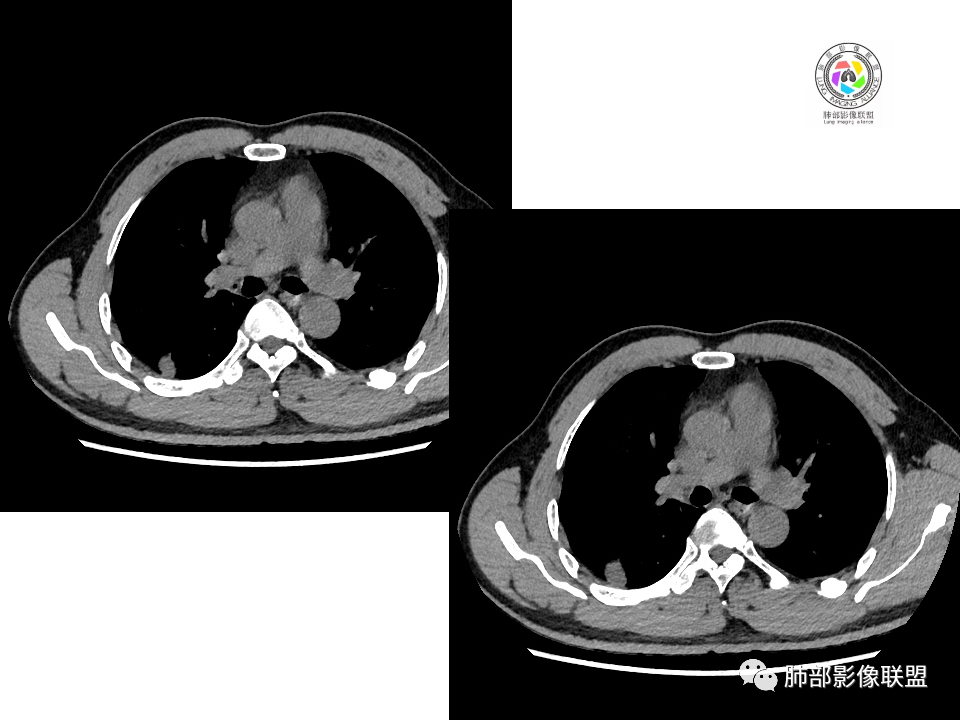

右肺下叶占位,胸膜下,与胸膜关系密切;

密度均匀;糊墙,边缘膨隆为主;

部分血管推移。

血管也是稍推移,在边缘,病灶密度均匀,边缘稍收缩;均匀强化;

这两个病灶的密度、强化、形态、边缘、与血管的关系类似;还是一元论吧。

②恶性:间叶来源肿瘤,间叶来源的两个病灶的罕见;癌一般还是与支气管关系密切,有如果考虑癌,自然是小细胞癌(山丘征);但是因为没有看到支气管具体情况,不太踏实。

2.右肺下叶背段胸膜下块影,边界清楚光整,上下极见磨玻璃晕,未见明显分叶毛刺和棘状突起,未见胸膜凹陷或胸壁侵入。密度均匀,轻度不均匀强化。未见支气管进入。

1.边缘光整干净,大病灶缺乏坏死等,不符合鳞癌影像学特征。尽管有吸烟史,还是偏年轻。

2.边缘光整,会是小细胞癌或是大细胞癌吗?小细胞癌的肺门纵隔淋巴结增大往往十分夸张,该患者不符合。